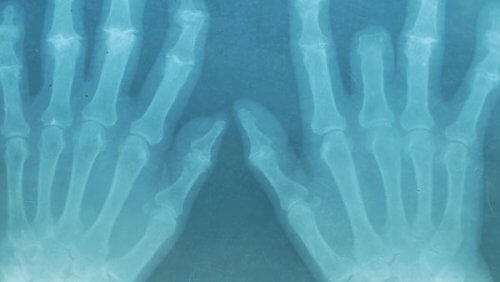

Розлади опорно-рухового апарату стають дедалі поширенішими з кожним днем. Їх можуть спричинити багато чинників: від травм після фізичного навантаження або поганої постави до природного погіршення, пов’язаного з віком. На жаль, немає ефективних довгострокових фармакологічних методів лікування цих розладів, тому ми рекомендуємо використовувати ефірні олії для зняття болю в м’язах і суглобах.